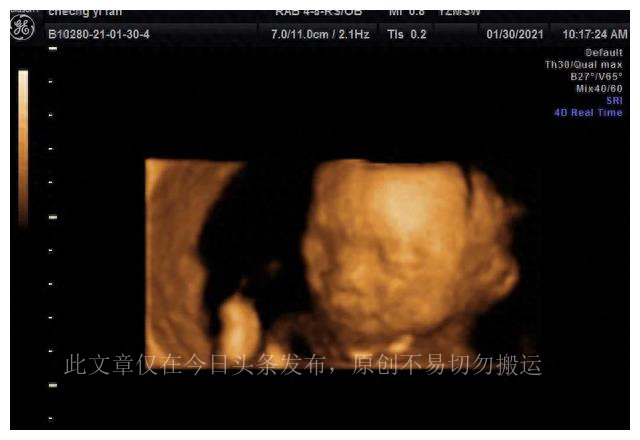

第二次四维检查在怀孕23周零4天进行,这次在一个私立医院进行。

主要原因是私立医院提供了保存胎儿照片和视频的选项。这次检查在早上进行,而这一次宝宝表现得非常配合。医生能够获得清晰的图像,包括宝宝的脸、脚和小拳头。医生还赞扬了宝宝的外貌特征,如尖尖的下巴、鼻梁和大眼睛。最后,宝宝甚至似乎对妈妈做出了一些可爱的手势,令未来的父母感到高兴。